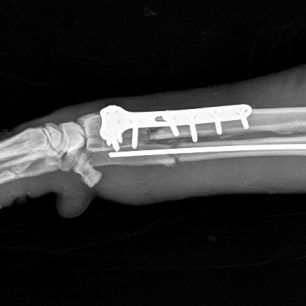

Η κα Μακρή δημοσίευσε σήμερα στο facebook την γνωμάτευση του κτηνιάτρου σχετικά με την εξέλιξη της υγείας του ζώου. Σε αυτή αναφέρεται ότι: «Ο σκύλος έφερε συντριπτικά ενδοαρθρικά κατάγματα με μετατόπιση στο κάτω τρίτο του αριστερού αντιβραχίου και στο κάτω τρίτο του αριστερού μηριαίου. Ολοκληρώθηκε με επιτυχία η πρώτη χειρουργική επέμβαση που αφορούσε την ανάταξη και οστεοσύνθεση του αριστερού αντιβραχίου. Λόγω της σοβαρότητας του κατάγματος η διάρκεια της χειρουργικής επέμβασης ήταν 4 ώρες και 25 λεπτά και ο σκύλος ανένηψε φυσιολογικά».